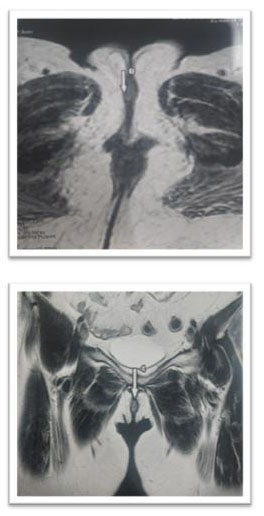

A vulvar biopsy was performed at this level, showing a well-differentiated verrucous carcinoma. The pelvic ultrasound was without abnormality, a pelvic and inguinal magnetic resonance image (MRI) was done highlighting a tissue thickening of the right labia minora with an intermediate signal on T2, in hypersignal intermediate apparent diffusion coefficient (ADC) diffusion, enhanced after injection of the phosphatidyl choline (PDC), measuring 20×17×6 mm. Laterally this process comes into contact with the large homolateral lip with loss of the fibrous border of separation. It respects the ureteral meatus (Figure 2).

Figure 2: Radiological appearance of the vulvar lesion.